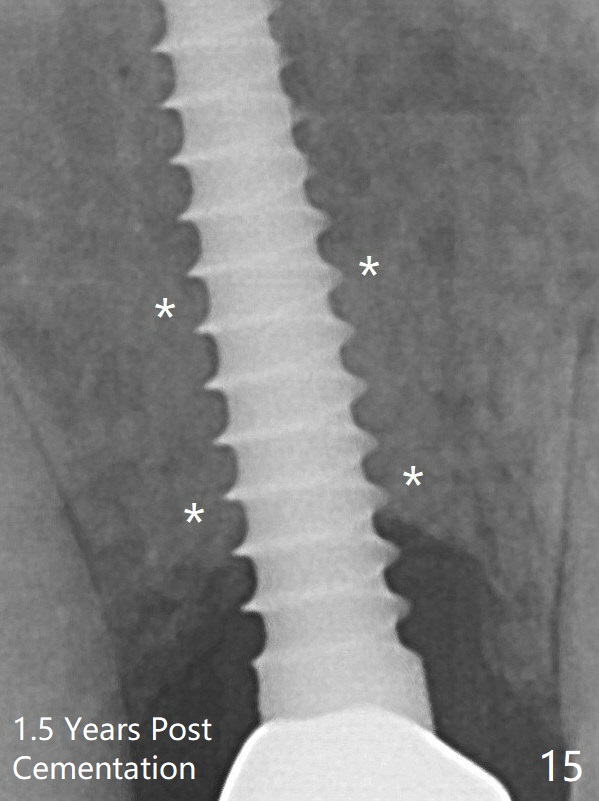

The peri-implant space (Fig.3) is filled with bone graft (Fig.4 *). The apical portion of the socket appears to have reduced 4 months postop (Fig.14). When the patient returns 1.5 years post cementation, there is increased bone density next to the coronal portion of the implant, equivalent to the bone graft (Fig.15 *). The crestal bone loss remains 2.5 years post cementation (Fig.17 *), although there is no sign of periimplantitis. Oral hygiene is poor.